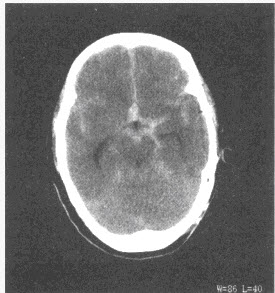

成人,外伤后1小时,CT检查如下图,最可能的诊断是()

A:硬膜下血肿

B:硬膜外血肿

C:蛛网膜下腔出血

D:正常脑CT

E:脑出血